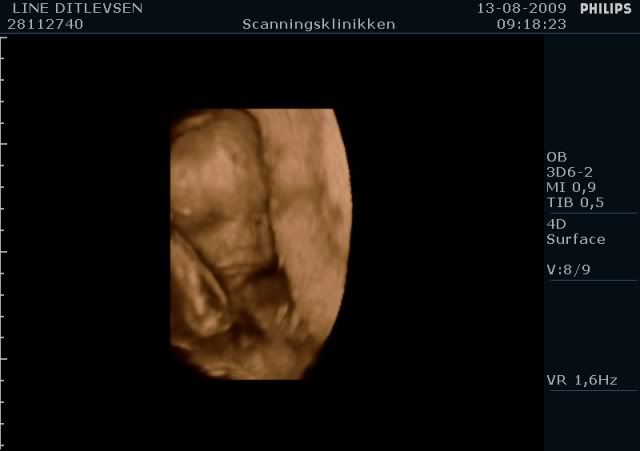

Jeg har lige været til en 3D/4D scanning (27+0), hvilket var en kæmpe oplevelse. Jeg venter en dreng på foreløbig 976 gram

Denne tråd er for alle os som har fået foretaget sådan en scanning. Jeg tænkte det kunne være sjovt at smide nogle fotos op af vores bebzere, da de lå i maven. I profil og forfra.

Skriv gerne hvilken uge scanningen er foretaget, samt evt. hvad køn det er